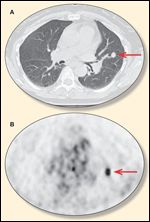

FIGURE 2

Chest Scans

How does metastatic urothelial carcinoma differ in radiologic appearance in the lung vs a primary lung lesion? Dr. Kimi L. Kondo: There is no specific radiologic characteristic that uniquely distinguishes a urothelial metastasis to the lung from a primary lung cancer. Pulmonary metastases tend to present as multiple lesions, although 5% of all solitary lung nodules are metastatic. Metastases typically have sharp margins and are usually located peripherally and in the lung bases; however, primary lung cancers can also have these characteristics. Nodules with increased 18F-fluorodeoxyglucose (FDG) uptake on positron-emission tomography (PET) are usually thought to be malignant, but inflammatory and infectious processes also can have increased FDG uptake. Biopsy and pathologic analysis are needed to distinguish a urothelial metastasis from a primary lung cancer. In our patient, the CT scan of the chest revealed a nodule with a corresponding hypermetabolic lesion on the FDG-PET scan (Figures 2A, 2B).

Dr. Thomas W. Flaig: In patients with metastatic disease, I generally initiate staging with a CT scan of the chest, abdomen, and pelvis plus a whole-body bone scan. In this case, an FDG-PET scan demonstrates the malignant deposit in her lung. There are limited data on the usefulness of PET scanning in urothelial cancer. However, the utility of PET scanning was recently examined preoperatively in patients with bladder cancer planning for cystectomy.[4] Occult metastatic disease was detected in 7 of the 42 subjects with negative CT imaging, yielding a sensitivity of 70% and specificity of greater than 90%. This suggests a potential role for PET imaging in urothelial cancer. What has your experience been with resecting metastatic transitional cell carcinoma in the lung?